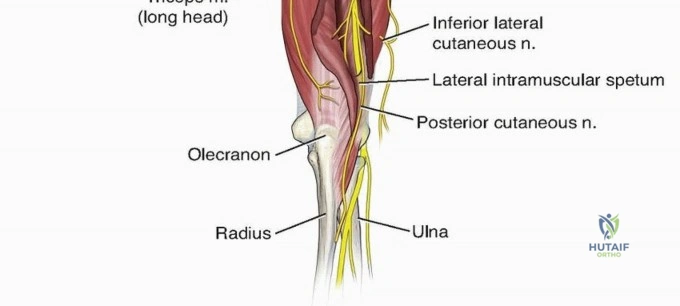

From the triangular interval, the radial nerve transverses from medial to lateral along the posterior aspect of the humeral shaft within the spiral groove. It pierces the lateral intermuscular septum approximately 10 to 12 centimeters proximal to the lateral epicondyle to enter the anterior compartment of the arm. Distally, the nerve travels in the anatomic interval between the brachialis muscle medially and the brachioradialis muscle laterally. This specific interval is the foundation of the distal anterolateral approach to the humerus.

For distal third fractures, the exposure must transition to the interval between the brachialis and the brachioradialis. The radial nerve emerges from the posterior compartment by piercing the lateral intermuscular septum and travels distally in the cleft between the brachialis (medially) and the brachioradialis (laterally).

To safely exploit this interval, the fascia between the brachialis and brachioradialis is carefully incised. The radial nerve must be actively identified and protected. It is often easiest to identify the nerve distally where the interval is wider and trace it proximally to where it pierces the septum. Once identified, the nerve is gently mobilized and protected with vessel loops. Retraction of the nerve must be minimal and meticulous to prevent iatrogenic neuropraxia.